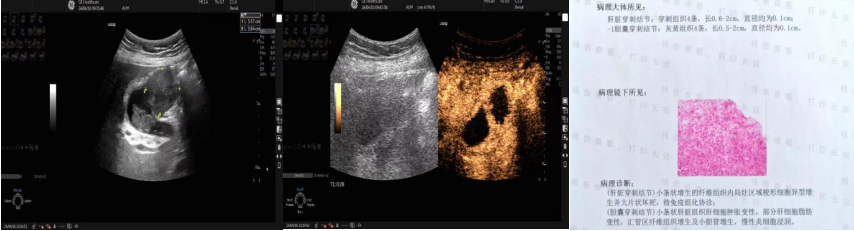

超声引导下经皮、经胃胰腺体尾部实性占位穿刺活检及穿刺病理结果

肿瘤科病区另一名68岁男性患者,超声及CT均提示胰腺体尾部占位,考虑恶性肿瘤,因肿瘤位置较深,位于胃后,且邻近脾动脉及脾静脉,穿刺风险较高,经魏炜教授周密评估后,在患者胃肠准备后行超声引导下经皮、经胃胰腺体尾部实性占位穿刺活检术,术后无并发症发生,在确保患者安全的同时,实现了精准穿刺活检,病理提示:纤维组织内见中分化腺癌浸润,为患者后续的精准治疗提供了有力的支持。